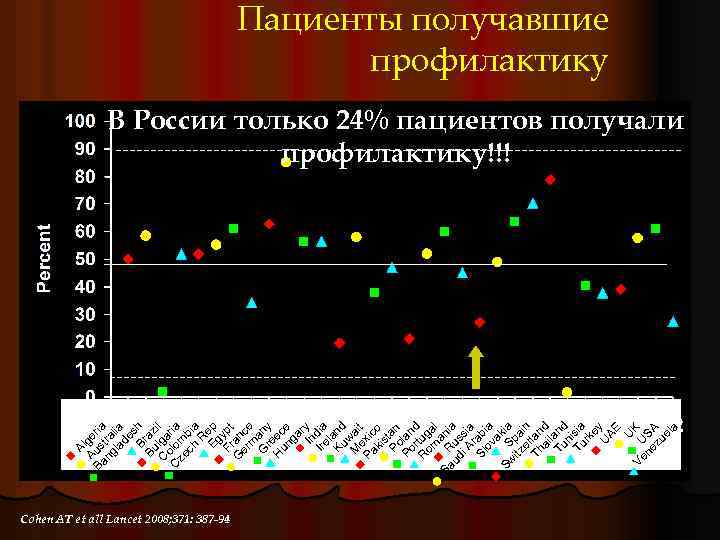

U Ve U K ne SA zu el a A Au lge Ba s ria ng tra la lia de s Br h Bu az C lga il C olom ria ze ch bia R Eg ep Fr ypt G an er ce m G any r H eec un e ga r In y Ire dia l Ku and w M ai ex t Pa ic ki o s Po tan Po lan r d R tug om a l Sa R ani ud us a i A sia r Sl ab ov ia a Sw S kia itz pa e in Th rlan ai d l Tu and n Tu isia rk e U y AE Пациенты получавшие профилактику В России только 24% пациентов получали профилактику!!! Cohen AT et all Lancet 2008; 371: 387 -94

Результаты ENDORS в России l Риск ВТЭ выявлен у 45, 7% пациентов У 52% хирургических l У 36. 7% терапевтических l l Профилактика проводилась только у 23, 8% пациентов l Более чем в 2 раза ниже среднего уровня мирового показателя l Примерно на одном уровне с Пакистаном, Индией и Венесуэлой